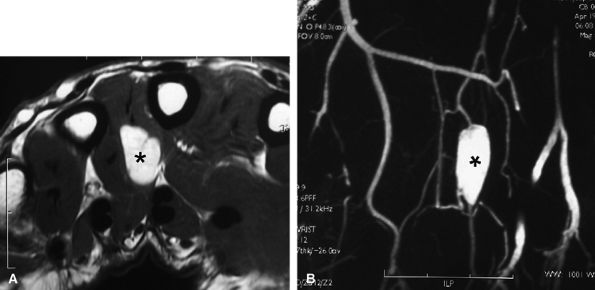

Articular, cartilaginous, or osseous invasion may also be depicted on MR studies (Fig. 11.77).

Venous malformations are frequently multifocal, have both intramuscular and subcutaneous components (see Fig. 11.77), and follow the neurovascular bundles of the affected limb.179

FIGURE 11.77 ● Venous malformation with bony involvement. Axial STIR (A) and coronal post-contrast fat-suppressed T1-weighted image (B) of vascular malformation infiltrating the thenar eminence, the three first metacarpals (arrows), and the subcutaneous tissues of the thumb (asterisks).